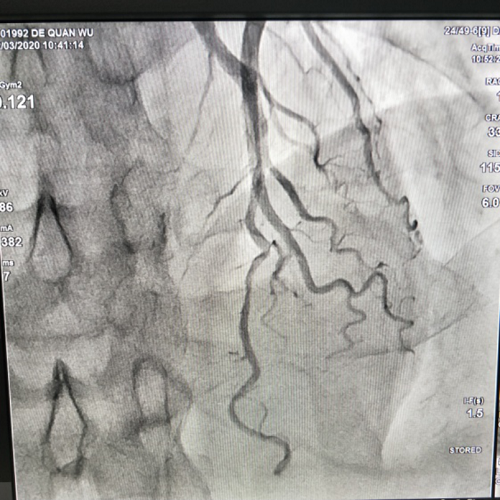

2020年3月12日上午,经过前期充分准备,涪陵区人民医院心血管内科副主任许宝安主治医师团队,成功为两例住院病人进行了冠状动脉造影检查,术后患者情况良好。冠心病心血管介入诊疗技术在医院首次开展,此次手术的成功,得力于院领导、各职能科室、医技科室的大力支持和心血管内科全体医务人员共同努力,标志着医院心血管内科整体水平迈上一个新的台阶。

心血管内科两名患者因反复心悸、胸闷不适入院,初步诊断为“冠心病”需做冠状动脉造影检查,经科内充分讨论,与患者及家属完善术前沟通,风险告知后进行冠脉造影检查,手术过程顺利,其中一名患者前降支中远段狭窄50-60%。

2.数字减影血管造影是一种可以看见实时纯血管清晰图像的诊疗技术,现已被广泛引用于呼吸、消化、肿瘤、神经、泌尿生殖及骨骼系统等诊断,冠状动脉的病变诊断和其他疾病的诊断及介入治疗,可以清晰的显示各种动脉瘤、动脉狭窄、闭塞、动静脉畸形等。